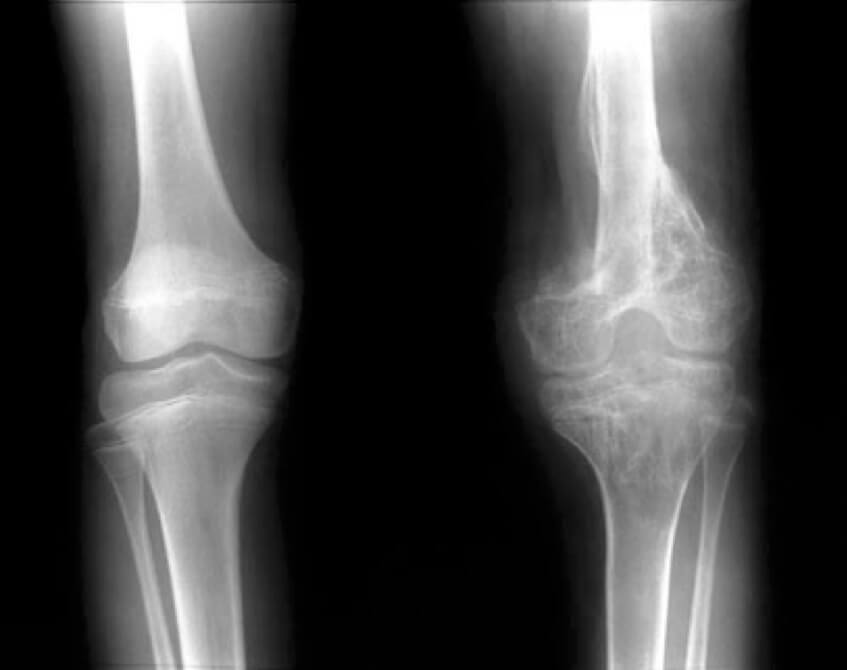

Οι ορθοπεδικές λοιμώξεις μπορεί να εκδηλωθούν με διάφορους τρόπους, ανάλογα με τη θέση και τη σοβαρότητα της λοίμωξης. Μερικά κοινά συμπτώματα περιλαμβάνουν πόνο, οίδημα, ερυθρότητα, ζεστασιά και ευαισθησία γύρω από την πληγείσα περιοχή. Σε πιο σοβαρές περιπτώσεις, η μόλυνση μπορεί να προκαλέσει πυρετό, ρίγη και άλλα συστηματικά συμπτώματα.